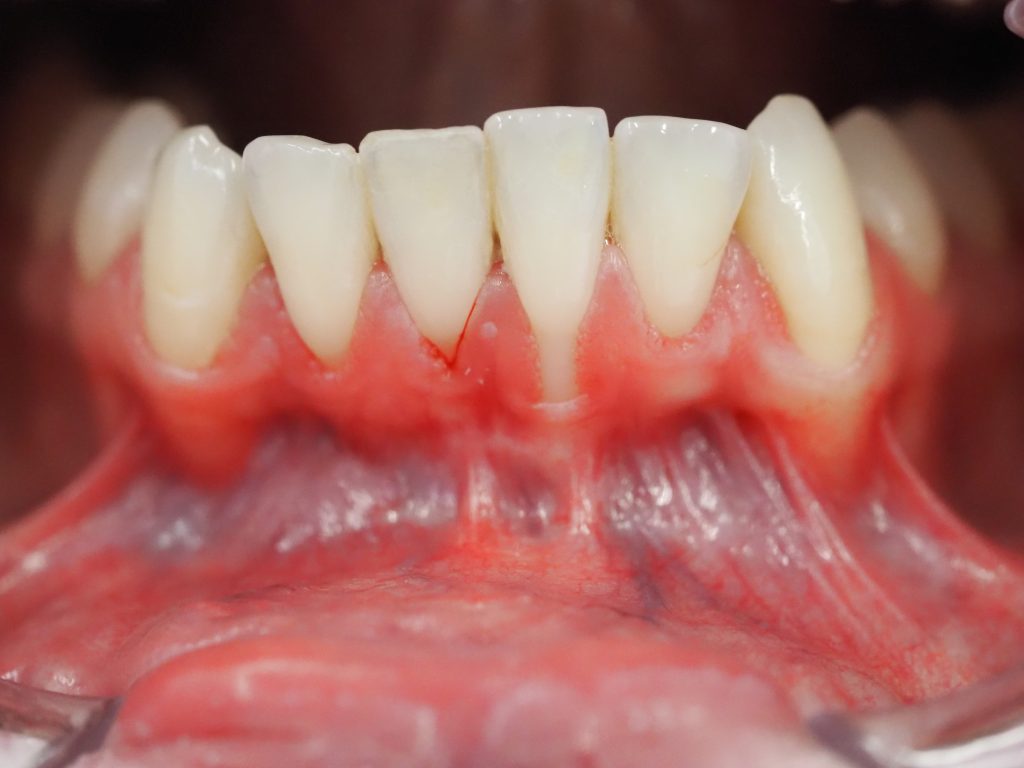

Recesión Gingival

CASO CLÍNICO

Recesión gingival incisivo inferior